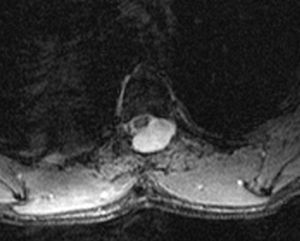

La resonancia magnética (RM) cerebral (Philips Intera 1,5 T) mostró una manifiesta hipointensidad lineal siguiendo las superficies leptomeníngeas vermianas y cerebelosas, y de forma menos extensa las superficies leptomeníngeas cerebrales, compatible con siderosis superficial por depósito de productos de degradación de la sangre. Discreto ensanchamiento de los surcos vermianos superiores y cerebelosos por atrofia focal. Dichos hallazgos eran más manifiestos en las secuencias T2 GE (fig. 1).

La RM cerebral practicada en el último ingreso fue definitiva para el diagnóstico al demostrar la siderosis, en especial cerebelosa (fig. 1). Examinadas con detalle las RM cerebrales realizadas en 1989 y 2000, se comprobó la presencia de débiles depósitos de siderina en el vermis y hemisferios cerebelosos, que en aquel momento no se valoraron. La gran sensibilidad de la RM para detectar el depósito de hemosiderina y ferritina permite el diagnóstico de siderosis superficial en el periodo presintomático que puede alcanzar 30 años. Ello podría explicar la ausencia de las manifestaciones clínicas más características en nuestro enfermo.